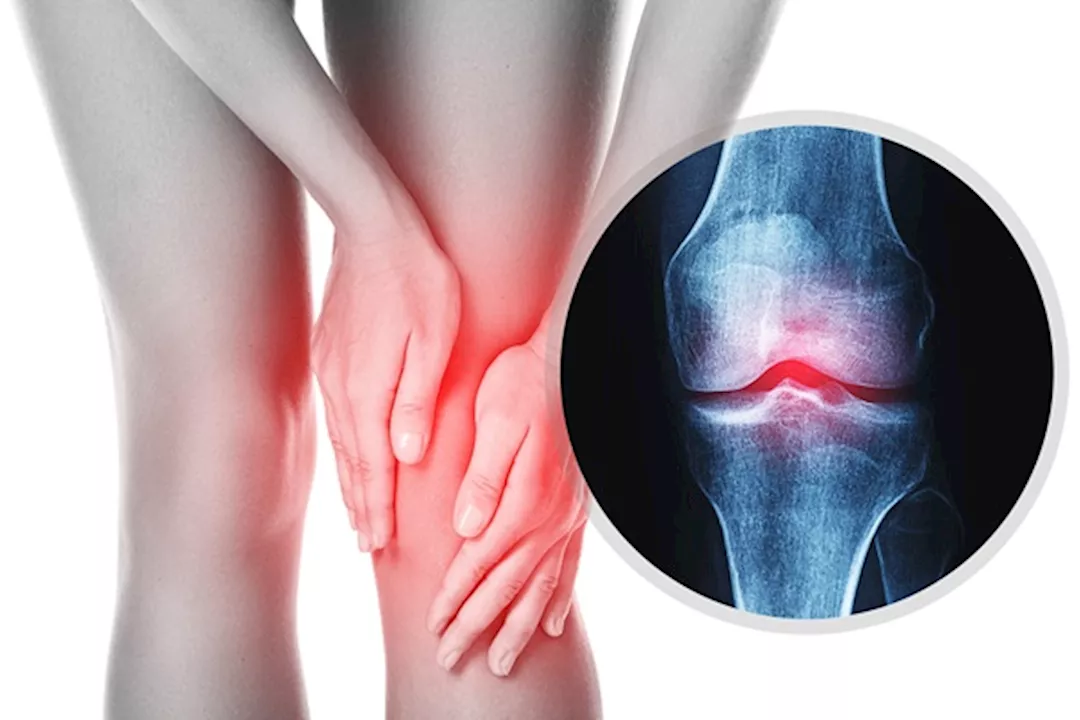

التهاب مفصل الركبة

كيف يمكنني منع التهاب المفاصل في ركبتي؟ هناك أطعمة تساعد على الوقاية، احرص على تناولها في النظام الغذائي اليومي.